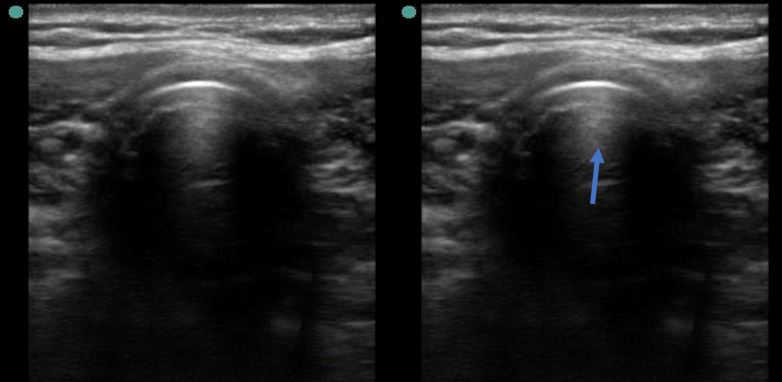

Se observa una única columna de gas, perteneciente a la tráquea (azul), sin identificarse gas en el esófago (estructura posterior y lateral a la tráquea).

Se realiza intubación orotraqueal sin incidencias, comprobándose posteriormente la correcta posición del tubo mediante el protocolo TRUE (Tracheal Rapid Ultrasound Scan). Este protocolo determina la presencia de una única columna de gas (indicando intubación endotraqueal correcta) o de una doble columna de gas, traqueal y esofágica (indica intubación esofágica, puesto que el esófago no genera artefacto de gas salvo que se encuentre intubado).